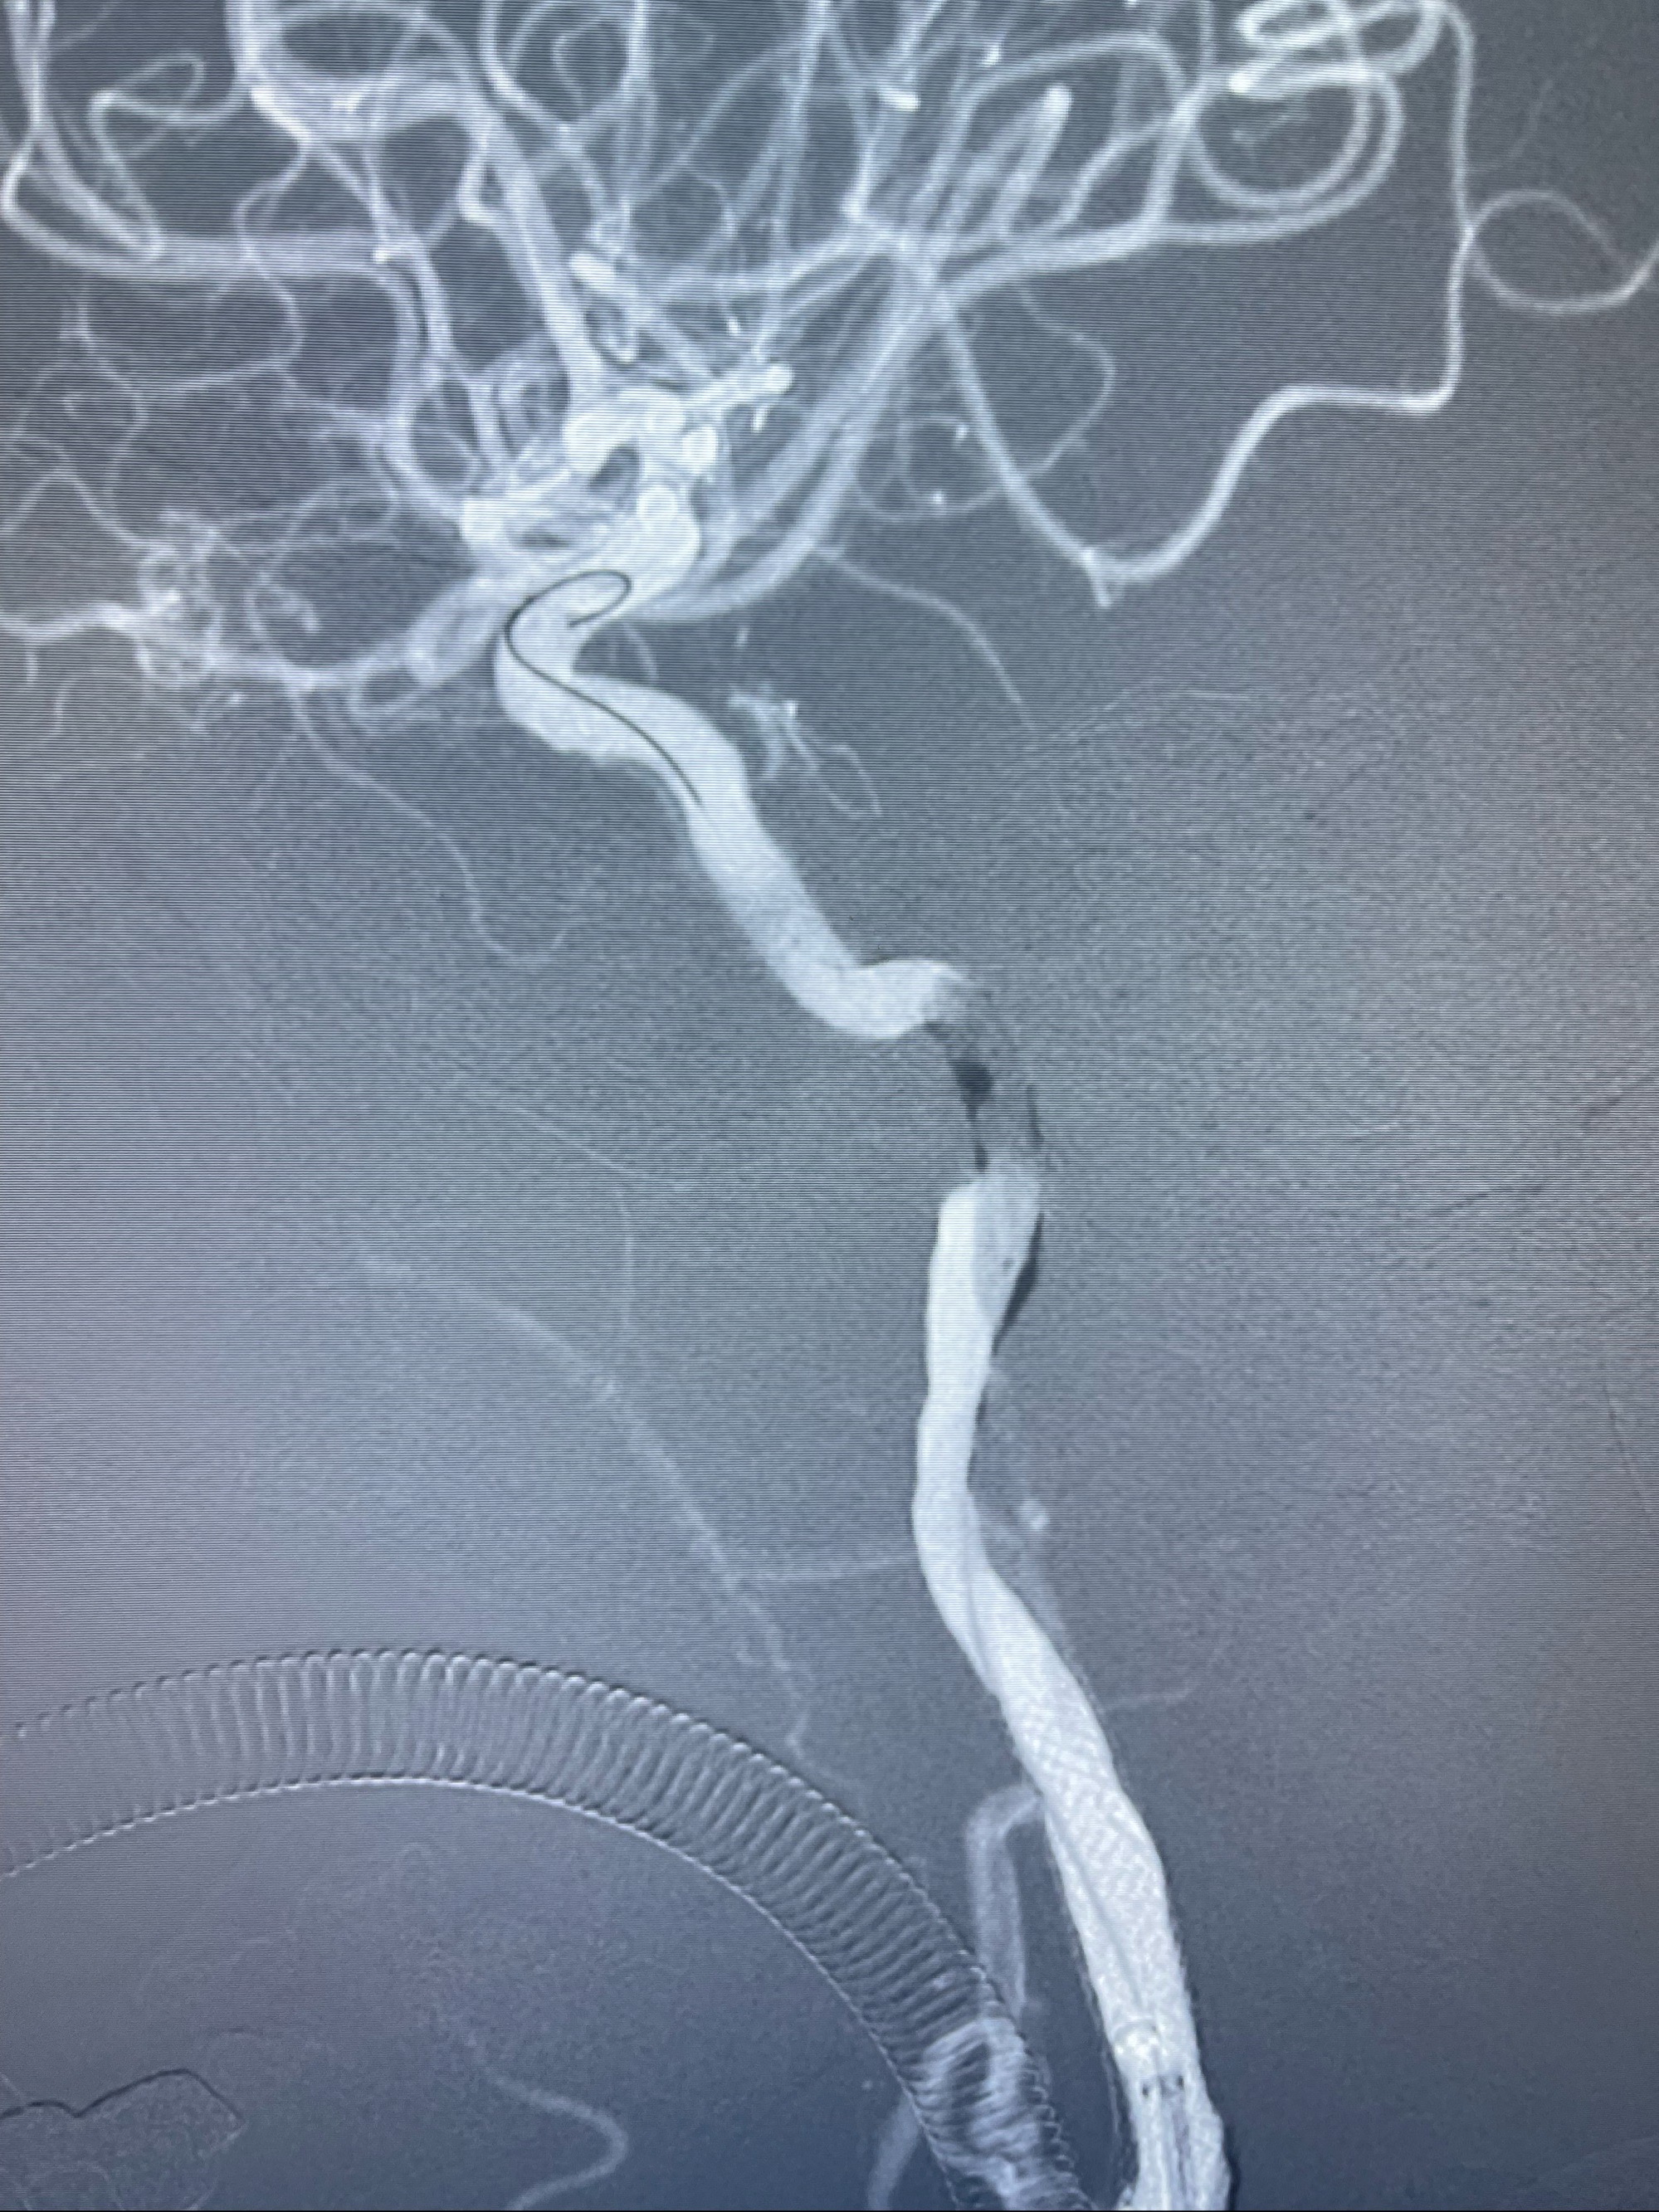

2023-07-10DSA:右侧颈内动脉岩骨段夹层伴中偏重度狭窄改变,左侧颈总动脉闭塞、右侧颈外动脉由右侧肋颈干甲颈干吻合代偿

箭头所示为颈内动脉岩骨段重度狭窄,结合MRI,考虑为肿瘤侵犯右侧颈内动脉

箭头以近至支架段管腔不规则狭窄